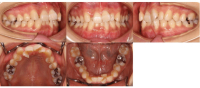

Before

After

| 年齢 | 範囲 | 抜歯有無 | 費用 |

|---|---|---|---|

| 23歳3ヶ月 | 全体矯正 | 非抜歯 | 80万円 |